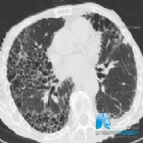

Foi aprovado no Brasil no final do mês de junho o uso do nintedanibe para o tratamento das doenças pulmonares intersticiais (DPIs) crônicas com fenótipo fibrosante progressivo. Isso significa que os pacient...